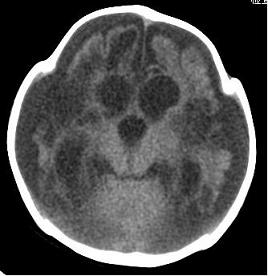

男,4个月大,2个月前无诱因下四肢抽搐、伴呕吐,近2天来抽搐频发,伴发热。查体:双眼疑视,神萎、纳差;颈抵抗,四肢张力高。

病史太长了,原因不好定,不过如果2个月前小儿正常的话可考虑积水型无脑畸形,积水型无脑畸形小儿刚生下来表现可正常,存活一两个月后出现症状.

另不除外缺血缺氧性脑病,感染等改变

2个月前缺血缺氧性脑病留下的后遗症。

脑出血后,软化灶形成了。脑发育不良

支持缺血缺氧性脑病留下的后遗改变(脑软化灶+脑发育不全+双侧慢性硬膜下积液+小头畸形)。

支持考虑缺血缺氧性脑病留下的后遗改变。

要注意化脓性脑膜、脑炎,硬膜下积脓,脑积水的可能,建议腰穿助诊。